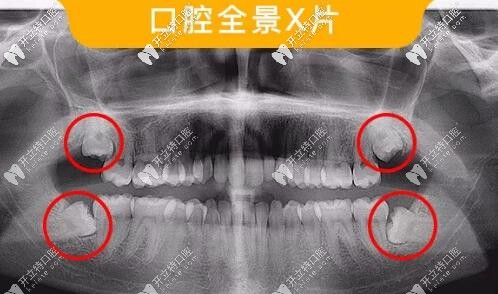

智齒口腔全景片

此類智齒需要拔除

如圖所示這樣沒有正常萌出,傾斜、阻生的智齒,容易造成食物鑲嵌堵塞,容易齲壞需要盡早拔除。

多生牙全景片